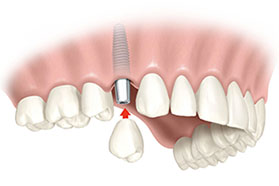

Los implantes dentales son aditamentos que funcionan como raíces artificiales, creados para sustituir dientes ausentes o perdidos por cualquier causa.

Se trata del método de reposición dental más avanzado para nuestra boca, ya que nos permite recuperar la estética y capacidad masticatoria de manera eficaz, cómoda y segura. Es muy recomendable reponer las piezas ausentes no sólo por una cuestión estética, sino también para poder masticar y digerir correctamente todo tipo de alimentos, lo que nos permitirá llevar una dieta sana y variada. La tecnología con la que trabajamos en la Clínica Dental Tresierra de la Rosa nos permite, en los casos en los que sea necesario y las características del paciente lo permitan, restaurar tu sonrisa en un solo día, mediante la realización de la implantología con carga inmediata.